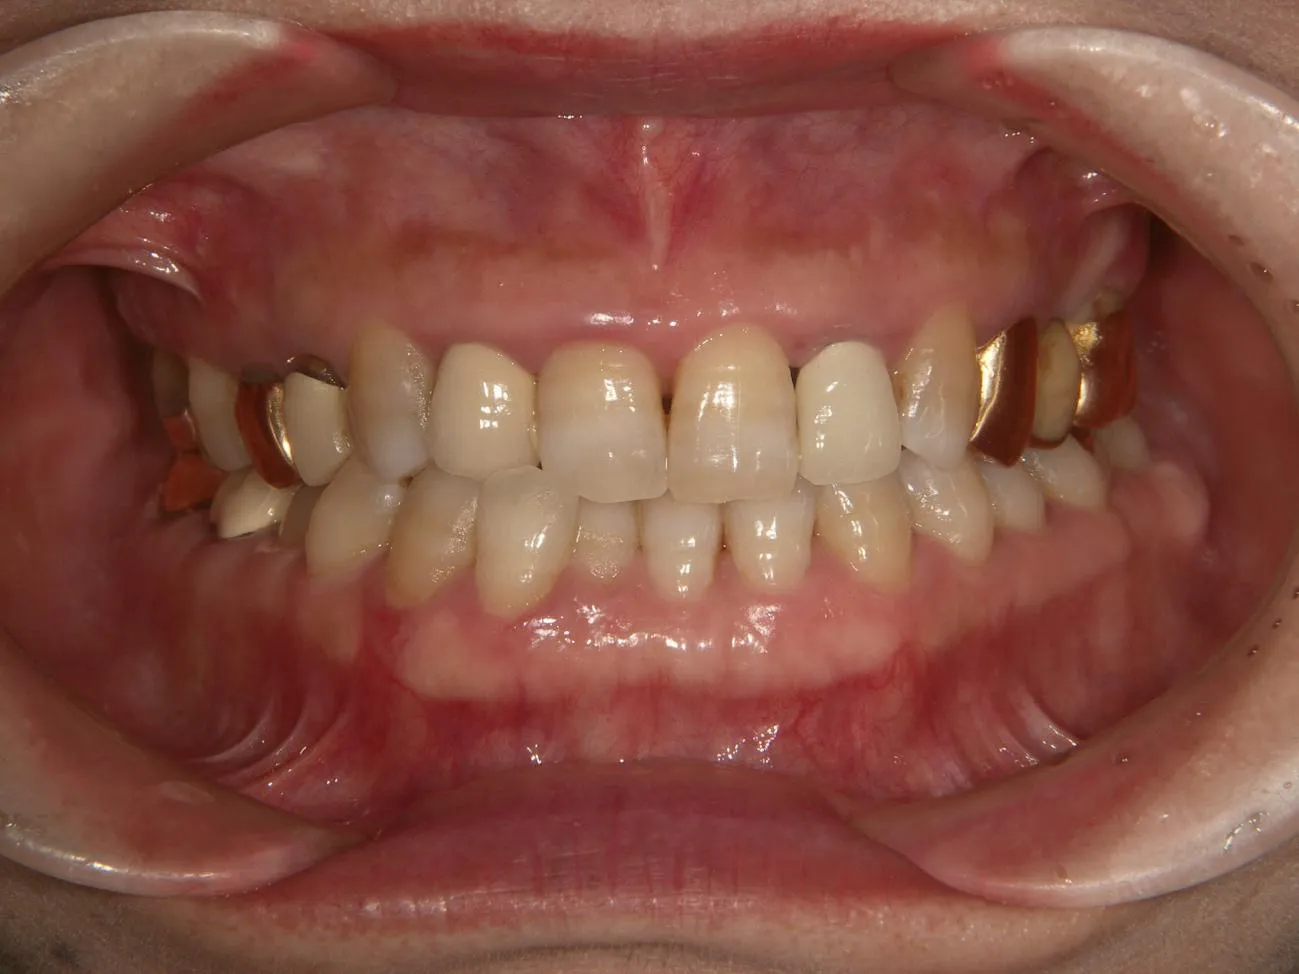

治療前